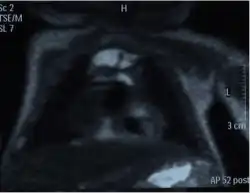

Magnetic resonance imaging (MRI) can be used to differentiate between a hemothorax and other forms of pleural effusion, and can suggest how long the hemothorax has been present for. Fresh blood can be seen as a fluid with low T1 but high T2 signals, while blood that has been present for more than a few hours displays both low T1 and T2 signals.[27] MRI is used infrequently in the trauma setting due to the prolonged time required to perform an MRI, and the deterioration in image quality that occurs with motion.[22]

Chest MRI showing a hemothorax in a 16-day-old infant